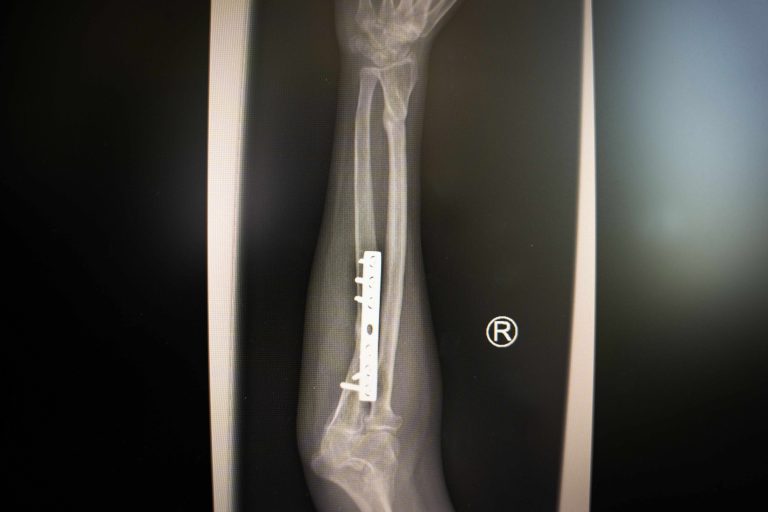

POS MB 708 12X-ray of Delay’s broken arm, survivor of extreme violencePOS MB 708 12$500

POS MB 708 13X-ray of Delay’s broken arm, survivor of extreme violence POS MB 708 13$500